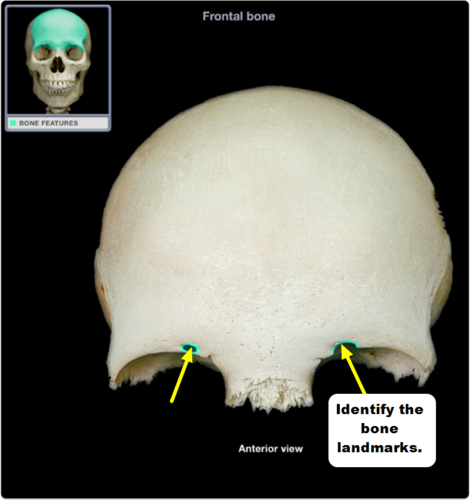

fovea trochlearis, trochlear fossa

two names for the small medial depression on the frontal bone behind the medial aspect of the superior orbital margin; the cartilaginous pulley for the tendon of the superior oblique muscle lies here in the anterior-medial portion of the orbital roof

fovea trochlearis

knowt flashcard image

29

New cards

lacrimal fossa